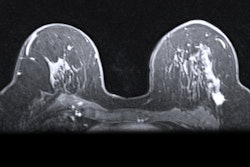

The platform uses dynamic contrast-enhanced MRI data to build patient-specific 3D digital models of breast cancer tumors and was initially cleared by the FDA in 2024.